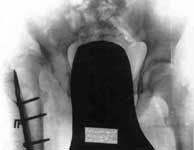

1.Врожденный вывих правого бедра, состояние после операции.

2.Операция Шанца-Илизарова с удлинением бедра.

3.Результат лечения.